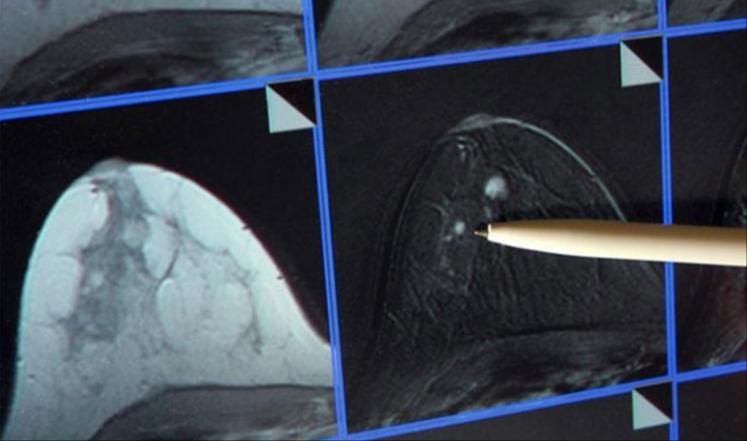

أفادت دراسة جديدة بأن نصف مرضى سرطان الثدي يمكن أن يستفيدوا من إضافة هرمون البروجسترون الأنثوي إلى علاجهم. فقد اكتشف العلماء أن هذا الهرمون يمكن أن يوقف نمو الورم.

وتظهر الدراسة الجديدة التي نشرتها صحيفة ديلي تلغراف البريطانية كيفية تخاطب مستقبلات هرمون البروجسترون مع المستقبلات الأخرى الحساسة للبروجسترون، التي تزيد سرطان الثدي في عدد كبير من الحالات، وهذا الأمر له تأثير استخدام المكابح على قدرة مستقبلات البروجسترون لتحفيز الأورام.

يشار إلى أن نحو 50 ألف حالة جديدة لسرطان الثدي تشخص في بريطانيا كل عام، ويعتقد الباحثون أن نحو النصف يمكن أن يستفيدوا من هذا الاكتشاف.

وهذا يعني إمكانية وقف المرض من الانتشار في بقية أجزاء الجسم، وهو ما يزيد الآمال في علاج جديد للمرض منقذ للحياة.